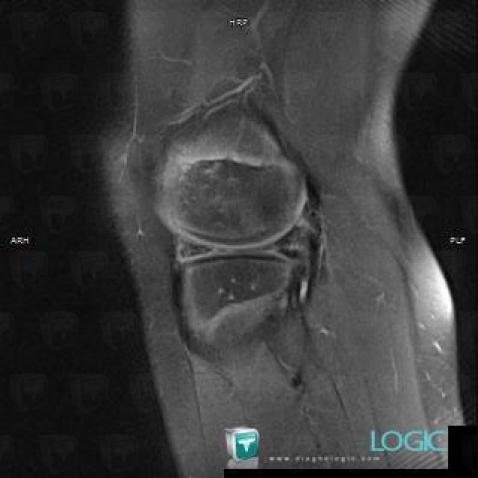

Horizontal-oblique meniscal tear, Meniscus, MRI

Here is the specific information in the key image above:

- Diagnosis Horizontal or oblique meniscal tear, Location(s) Meniscus, with gamuts Meniscal injury